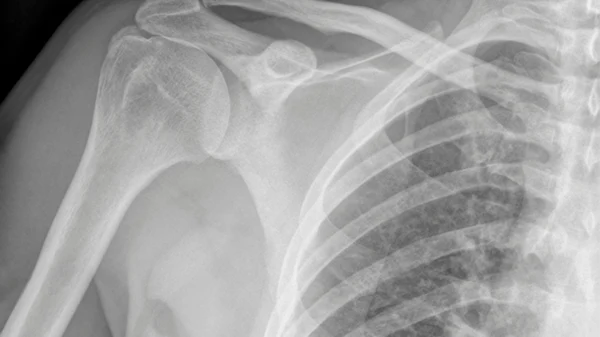

Shoulder: Rotator Cuff Repair Surgery

What Does Surgery Involve for Me?

1. Incisions: Small incisions are made to access the torn rotator cuff.

2. Tendon Reattachment: The torn tendon is reattached to the bone using sutures or anchors.